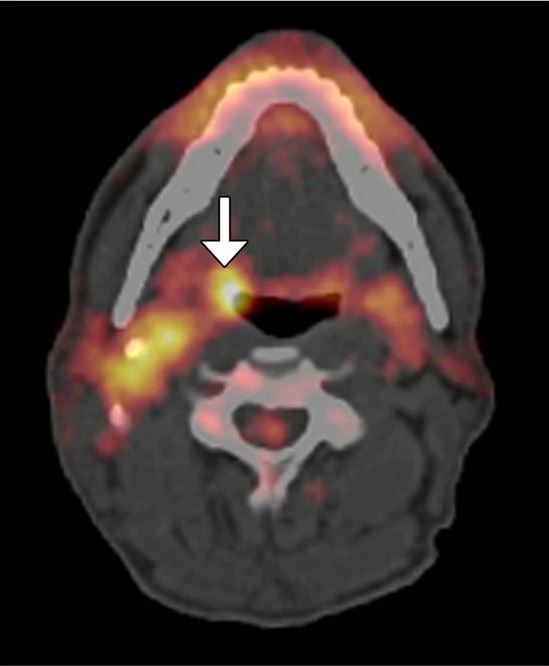

In 2017, the World Health Organization (WHO) updated their nomenclature and made changes such as refining terminology of existing entities, adding descriptions of new tumor types, eliminating defunct categories, and updating biological characterization of various tumor types. Therefore, this article set out to review the imaging features of head and neck lesions with the new updated nomenclature.